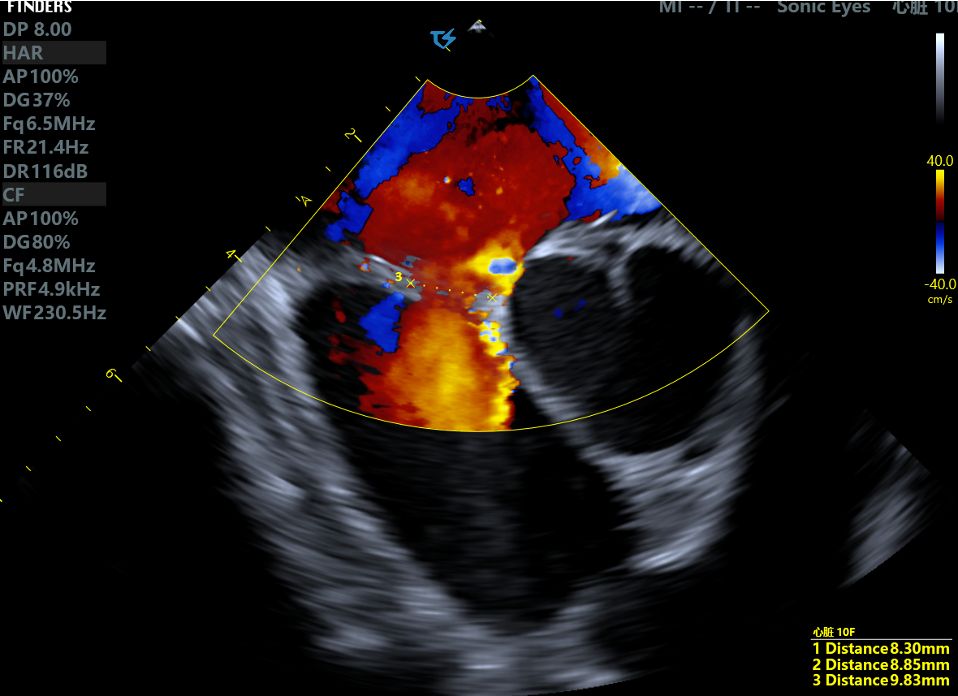

Clinical Strategy: During the procedure, intraoperative ICE ultrasound was used to reassess the defect size, measuring 9.83mm with a soft margin. Given the patient's young age and comprehensive evaluation, we selected the BDASD-I 16 (waist diameter is 16mm) biodegradable ASD occluder as the optimal solution for this case.

Case Summary: In the field of interventional cardiology, intracardiac echocardiography (ICE) has become an invaluable tool, offering high-resolution, real-time imaging to precisely visualize defects. In this case, ICE and TTE were used from multiple views and angles to confirm the positioning of the double-disc occluder, ensuring that it was properly bridged across both sides of the septum. Upon release, the occluder was observed to be securely attached to the septum with no residual shunt, allowing for an efficient and successful closure.